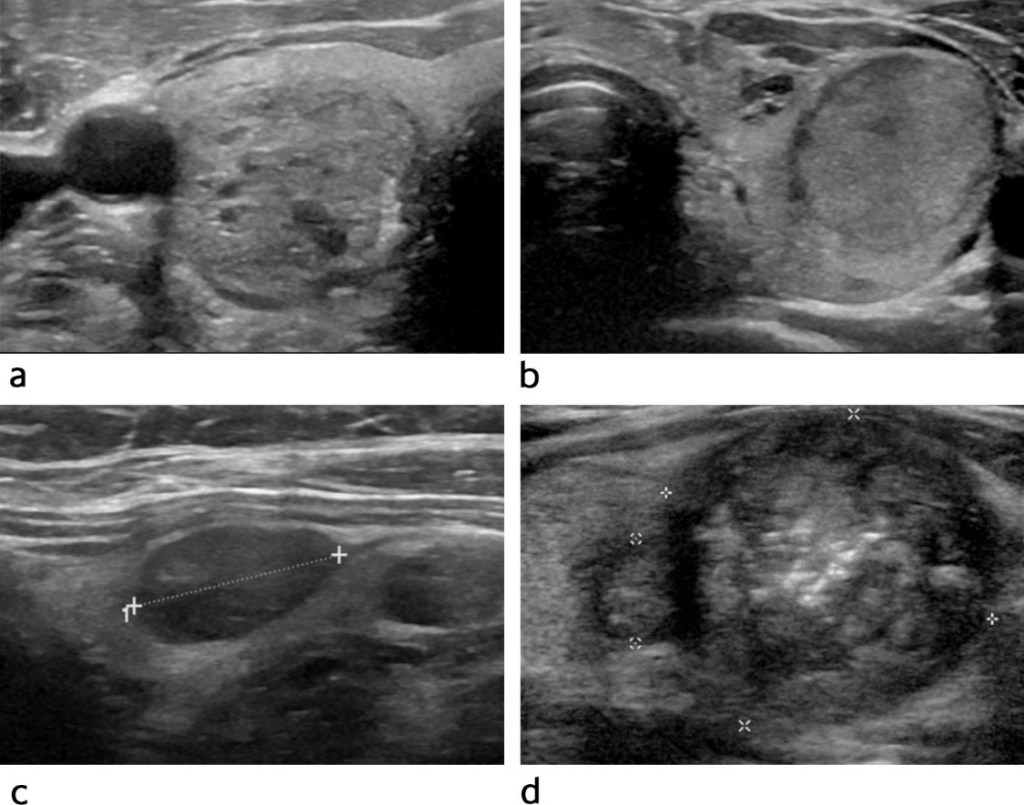

The first and most important test is a high-resolution thyroid ultrasound. It allows us to:

Accurately characterize the nodule (size, margins, echogenicity, calcifications) Stratify cancer risk using validated systems (such as ATA or TI-RADS) Determine whether a biopsy is necessary

If the ultrasound shows suspicious features, a ultrasound-guided fine-needle aspiration biopsy (FNAB) is recommended.